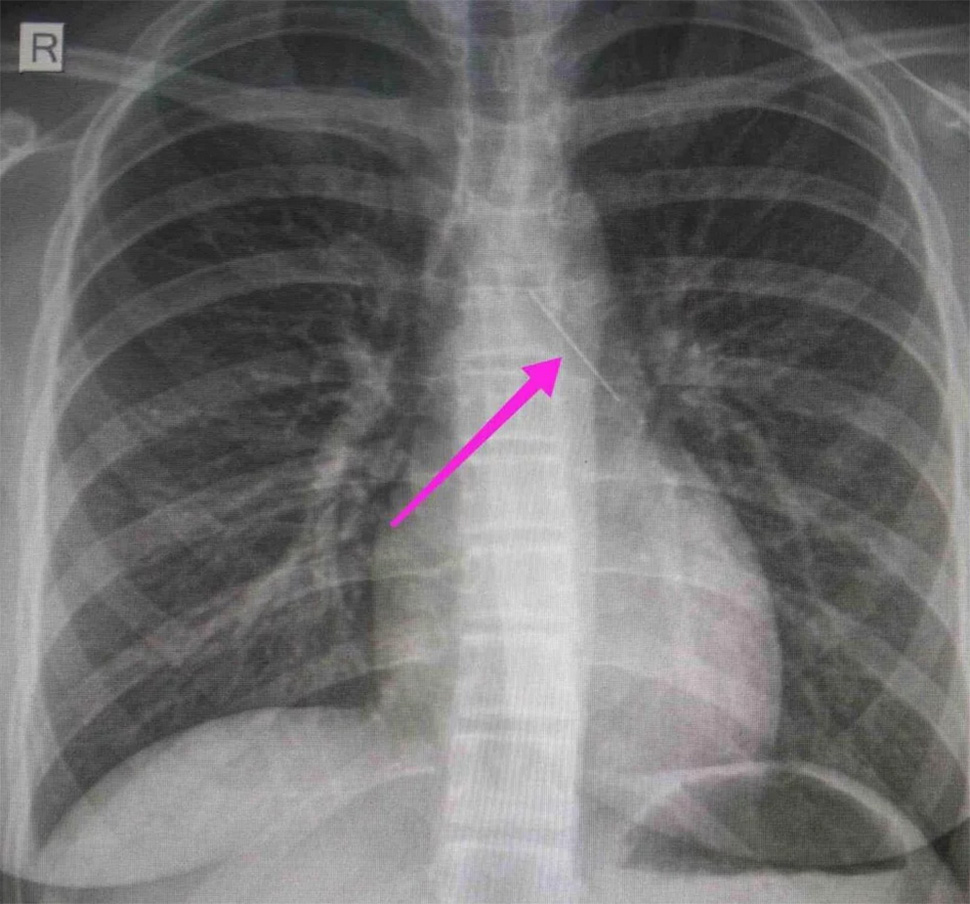

Από την ακτινογραφία θώρακος και την αξονική τομογραφία θώρακος, διαπιστώθηκε «η ύπαρξη αιχμηρού μεταλλικού ξένου σώματος στην αναπνευστική οδό (αριστερός κύριος βρόγχος) και όχι στην πεπτική οδό», αναφέρει η ανακοίνωση του νοσοκομείου, στα μέσα κοινωνικής δικτύωσης, όπου δημοσιεύονται και οι παρακάτω εικόνες.

Η ανήλικη υπεβλήθη σε βρογχοσκόπηση και διαπιστώθηκε η μετακίνηση και ενσφήνωση του αντικειμένου στον δεξιό κύριο βρόγχο. «Μετά οπό εργώδεις προσπάθειες ολοκληρώθηκε με επιτυχία η αφαίρεσή της», δηλώνει το νοσοκομείο.

«Χθες 30/1/2022 στις 16:00 στο Τ.Ε.Π. του ΓΝΘ Ιπποκράτειο, προσήλθε ανήλικη συνοδευόμενη από τους γονείς της, μετά από αναφερόμενη κατάποση ξένου σώματος (καρφίτσα). Από την απεικονιστική διερεύνηση που πραγματοποιήθηκε με ακτινογραφία θώρακος αρχικά και ακολούθως με αξονική τομογραφία θώρακος, διαπιστώθηκε η ύπαρξη αιχμηρού μεταλλικού ξένου σώματος στην αναπνευστική οδό (αριστερός κύριος βρόγχος) και όχι στην πεπτική οδό.

Κατά την βρογχοσκόπηση διαπιστώθηκε η μετακίνηση και ενσφήνωση του ξένου σώματος στον δεξιό κύριο βρόγχο. Μετά από εργώδεις προσπάθειες ολοκληρώθηκε με επιτυχία η αφαίρεση αυτού. Η ασθενής ανένηψε πλήρως εντός της χειρουργικής αίθουσας. Η ασθενής μεταφέρθηκε για παρακολούθηση και νοσηλεία στη Γ’ Παιδιατρική Κλινική.